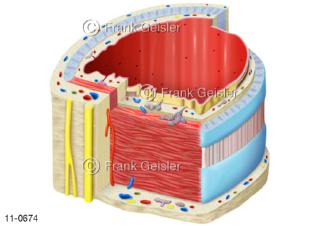

11-0674 Anatomie Luftröhre Trachea mit Knorpelspangen Muskelgewebe und Schleimhäute als 3D-Schnitt